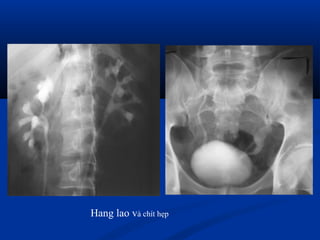

Lao niLao niệuệu

 Phân loại Elke :Phân loại Elke :

 Stade I : lao thận, X quang bình thườngStade I : lao thận, X quang bình thường

 Stade II : lao tạo hang (phá hủy < 1/3 thận)Stade II : lao tạo hang (phá hủy < 1/3 thận)

 Stade III : thận mủ > 1/3 thận (néphrectomie)Stade III : thận mủ > 1/3 thận (néphrectomie)

 UIV : khám nghiệm lựa chọn (vôi hoá, chít hẹp,UIV : khám nghiệm lựa chọn (vôi hoá, chít hẹp,

hình cộng..)hình cộng..)

Hang lao và chít hẹp

Lao niệu quản